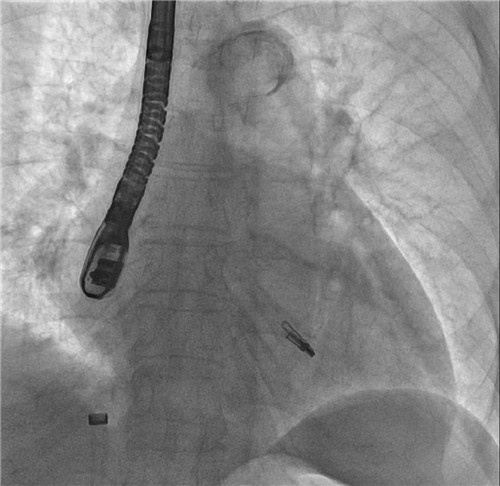

钳子DSA影像

不开刀,极低射线,无需体外循环,无需心脏停搏,全程超声引导。7月9日上午,湖南省人民医院心内科团队为一名重度二尖瓣关闭不全伴心力衰竭的高龄患者,成功施行经导管二尖瓣缘对缘修补术,即二尖瓣钳夹术((MitraClip)。这也是湖南省人民医院心内科完成的首例高难度经导管二尖瓣钳夹术,标志着该团队在结构性心脏病微创治疗领域的重大突破。

7月9日上午,心内科联合麻醉科、胸外科等多学科,共同为陈奶奶开展手术,术前二尖瓣大量反流,反流程度5+,肺静脉反流明显,术后二尖瓣少量反流,反流程度1+,肺静脉反流消失,手术顺利结束。术后安返病房,次日陈奶奶从不能平卧到能下床活动。在医护人员的精心照顾下,陈奶奶现已顺利出院。